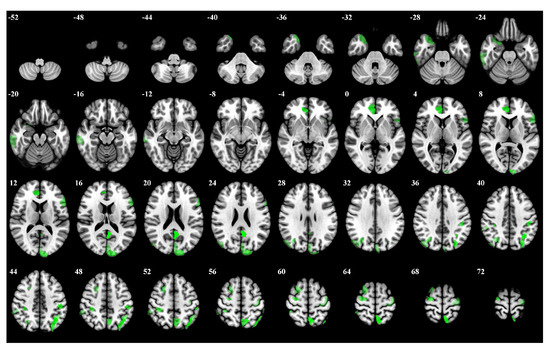

| Rank | Brain Regions | Side | Centroid Coordinates (R A S) | Importance Weight |

|---|---|---|---|---|

| 1 | Default Precuneus Posterior Cingulate Cortex 3 | L | −4 −53 20 | 0.246 |

| 2 | Frontoparietal Control Parietal 4 | L | −35 −62 48 | 0.241 |

| 3 | Dorsal Attention Posterior 15 | L | −7 −59 63 | 0.237 |

| 4 | Limbic Temporal Pole 2 | L | 7 42 4 | 0.216 |

| 5 | Dorsal Attention Posterior 8 | L | −46 −29 44 | 0.212 |

| 6 | Frontoparietal Control Parietal 1 | L | −29 −74 42 | 0.211 |

| 7 | Somatomotor 31 | R | 29 −11 65 | 0.206 |

| 8 | Visual 24 | L | −11 −97 17 | 0.195 |

| 9 | Frontoparietal Control Precuneus 2 | L | −5 −64 52 | 0.187 |

| 10 | Dorsal Attention Posterior 13 | R | 35 −36 51 | 0.181 |

| 11 | Limbic Temporal Pole 5 | R | 29 12 −30 | 0.176 |

| 12 | Frontoparietal Control Parietal 5 | L | −42 −52 49 | 0.174 |

| 13 | Dorsal Attention Posterior 5 | R | 32 −66 35 | 0.171 |

| 14 | Default Prefrontal Cortex 10 | L | −53 19 11 | 0.169 |

| 15 | Frontoparietal Control Lateral Prefrontal Cortex 15 | R | 24 10 58 | 0.165 |

| 16 | Frontoparietal Control Temporal 1 | R | 62 −28 −20 | 0.163 |

| 17 | Somatomotor 26 | L | −36 −19 65 | 0.161 |

| 18 | Visual 25 | L | −3 −84 24 | 0.159 |

| 19 | Dorsal Attention Posterior 4 | R | 45 −75 31 | 0.157 |

| 20 | Frontoparietal Control Parietal 2 | R | 56 −41 48 | 0.153 |